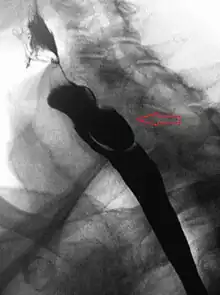

If small (ie, <2 cm) and asymptomatic, no treatment is necessary.[5] Larger, symptomatic cases of Zenker's diverticulum have been traditionally treated by neck surgery to resect the diverticulum and incise the cricopharyngeus muscle. However, in recent times non-surgical endoscopic techniques have gained more importance (as they allow for much faster recovery), and the currently preferred treatment is endoscopic stapling[6][7] (i.e. diverticulotomy with staples ). This may be performed through a diverticuloscope. Other methods include fibreoptic diverticular repair.[8]

Other non-surgical treatment modalities also exist, such as endoscopic laser, which recent evidence suggests is less effective than stapling.[9]